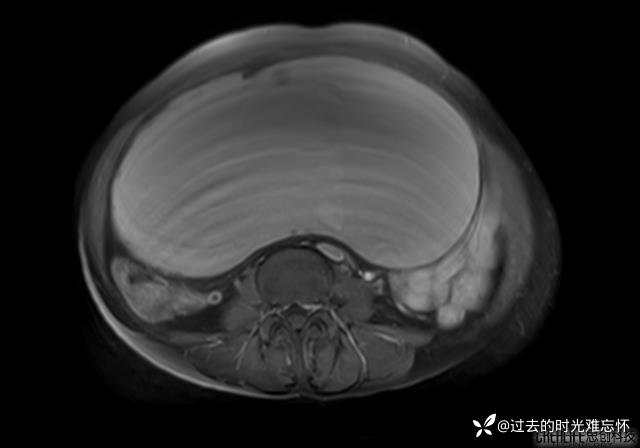

患者性别:女

患者年龄:65岁

主诉: 发现腹部隆起半年余。无其他明显不适。

浆液性囊腺瘤 (22)